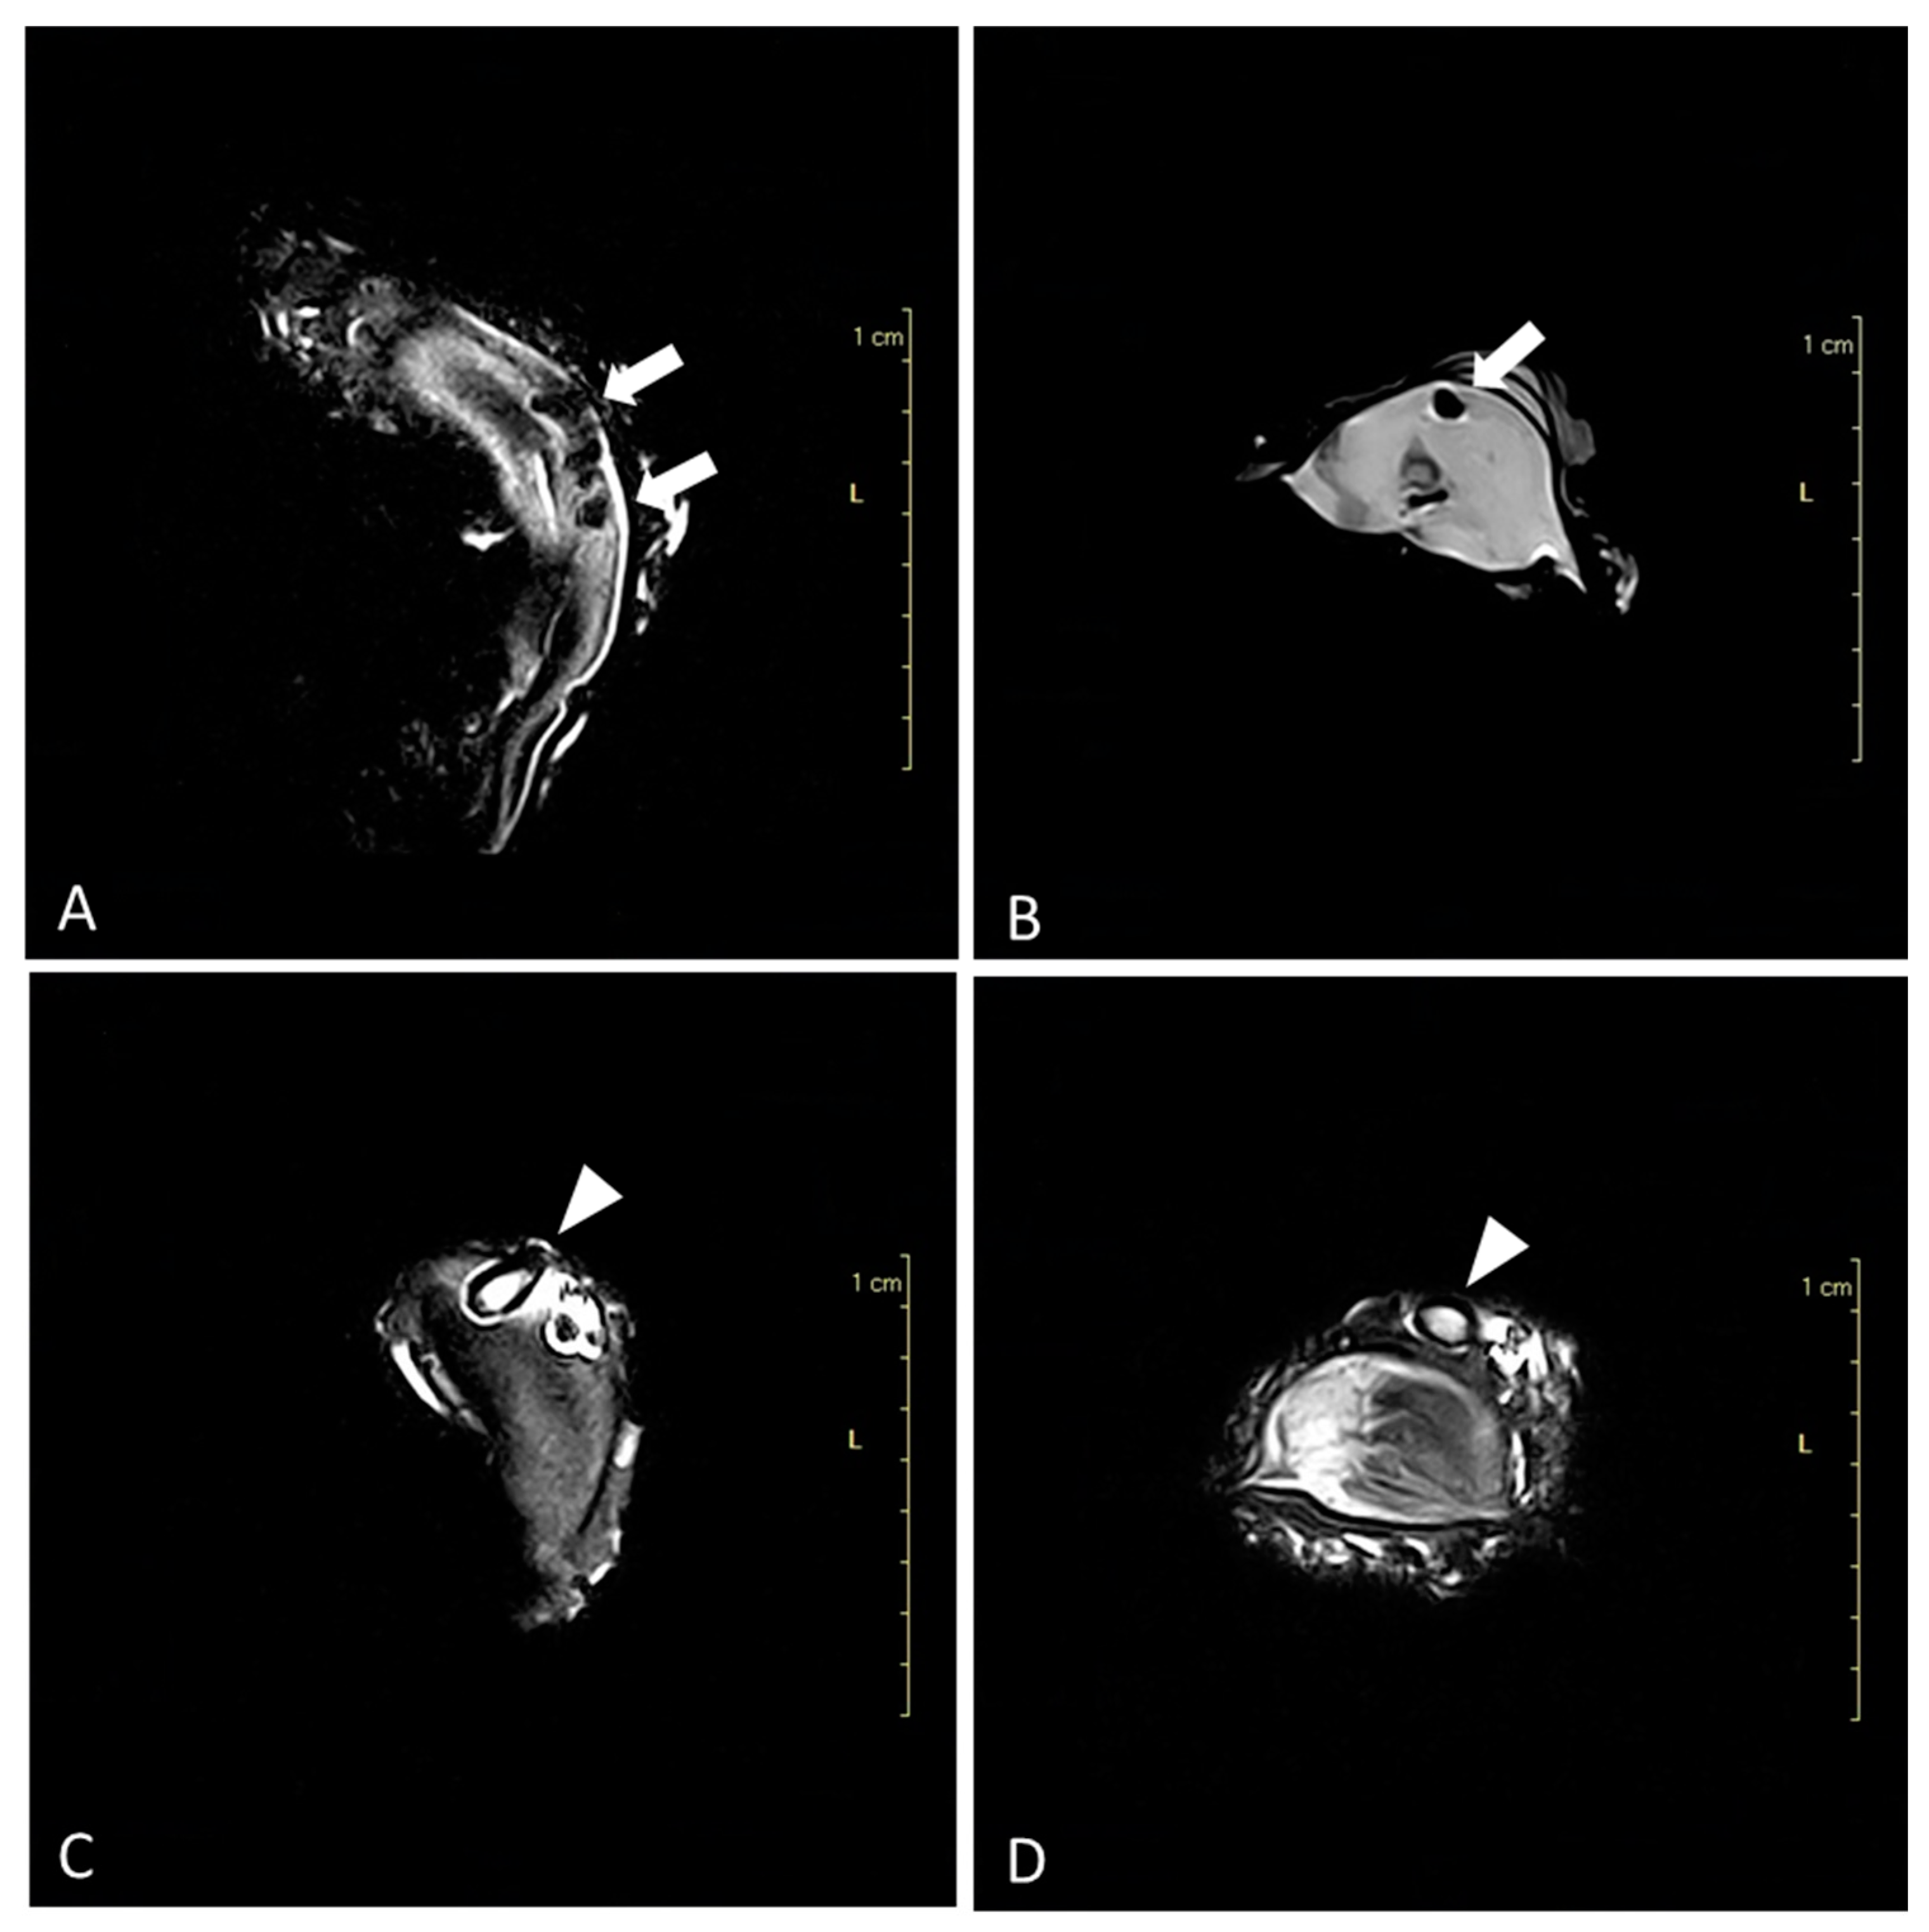

3.1. Advanced Diagnostic Techniques

3.2. Macroscopic Findings